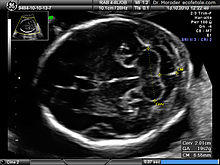

Ultrasound image of the fetal head at 19 weeks of pregnancy in a modified axial section, showing the normal fetal cerebellum and cisterna magna

Congenital malformation, hereditary disorders, and acquired conditions can affect cerebellar structure and, consequently, cerebellar function. Unless the causative condition is reversible, the only possible treatment is to help people live with their problems.[60] Visualization of the fetal cerebellum by ultrasound scan at 18 to 20 weeks of pregnancy can be used to screen for fetal neural tube defects with a sensitivity rate of up to 99%.[61]